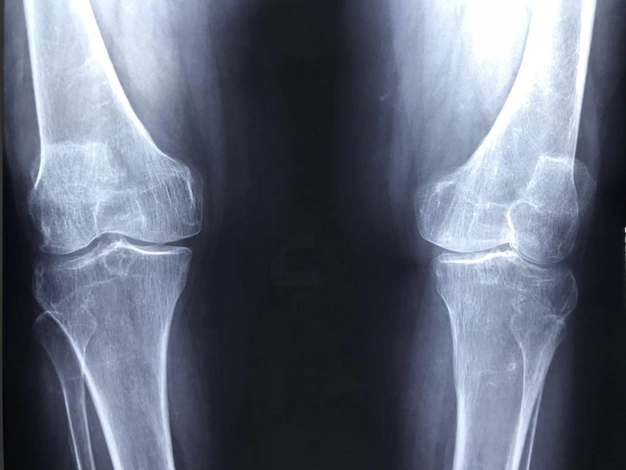

Reemplazo de cadera o rodilla

Cuando la cadera duele tanto que ya no puedes caminar bien, se puede poner una nueva articulación para recuperar el movimiento. Si tus rodillas están muy desgastadas y cada paso duele, es posible colocar una prótesis para volver a moverte sin dolor.

Cambio de prótesis de cadera y rodilla

Si ya tienes una prótesis pero volvió el dolor o dejó de funcionar bien, se puede revisar y cambiar si es necesario.